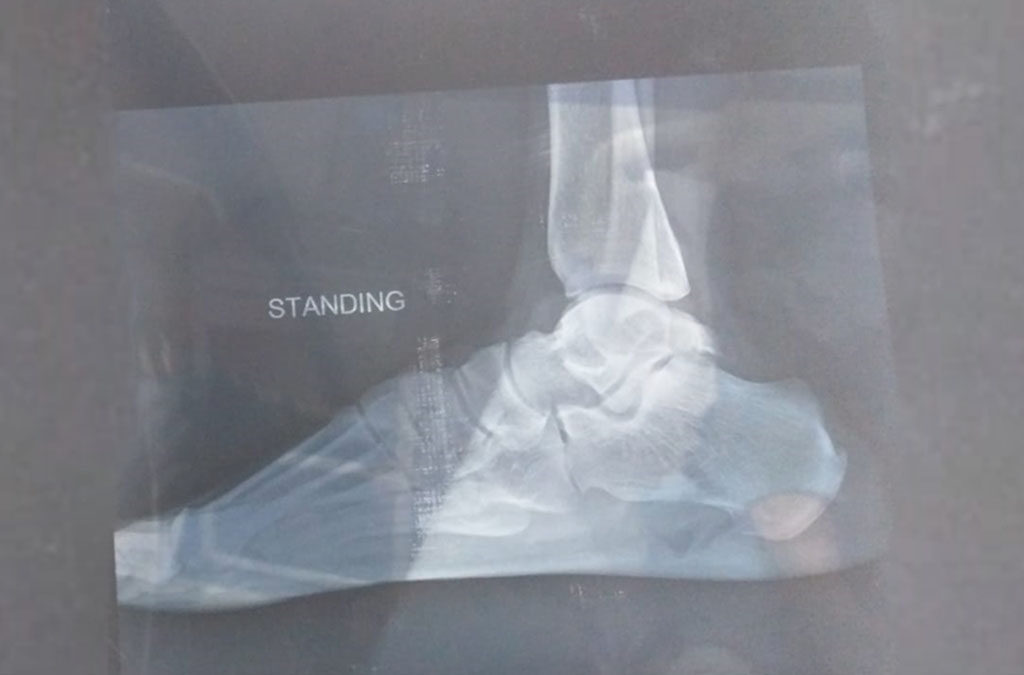

Talus Bone Manipulation . talus is a pivotal bone that assists in easy and correct locomotion and transfers body weight from the shin to the. Simple osteochondral fractures of the talar body often are subtle and only discovered after a long history of. the talus or ankle bone is an irregularly shaped bone which forms the link between the foot and the leg through the ankle joint. osteochondral lesions of the talus (olt) involve the subchondral bone and the overlying articular cartilage. talus fractures represent a challenging and heterogeneous group of injuries. the talus ranks as the second largest tarsal bone with unique anatomic features and.

the talus or ankle bone is an irregularly shaped bone which forms the link between the foot and the leg through the ankle joint. the talus ranks as the second largest tarsal bone with unique anatomic features and. Simple osteochondral fractures of the talar body often are subtle and only discovered after a long history of. osteochondral lesions of the talus (olt) involve the subchondral bone and the overlying articular cartilage. talus fractures represent a challenging and heterogeneous group of injuries. talus is a pivotal bone that assists in easy and correct locomotion and transfers body weight from the shin to the.